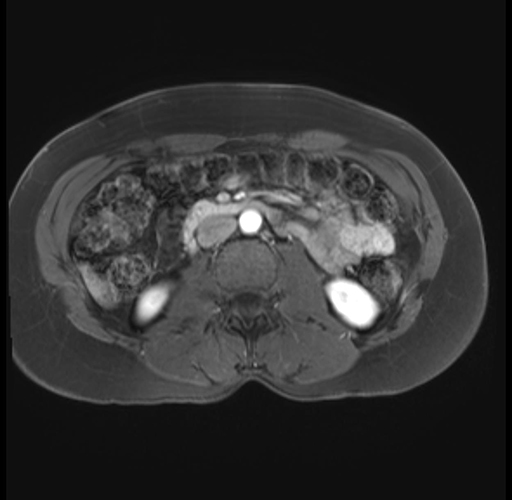

Imaging Analysis

Look through the patient's CT scan to identify any areas of concern for the necessary procedure.

Based on your CT findings, which issue(s) are present and would give reason for "planned slowing down moment(s)" in this case?

Considering a standard distal pancreatectomy procedure, what step(s) of the operation would you do differently in this case?